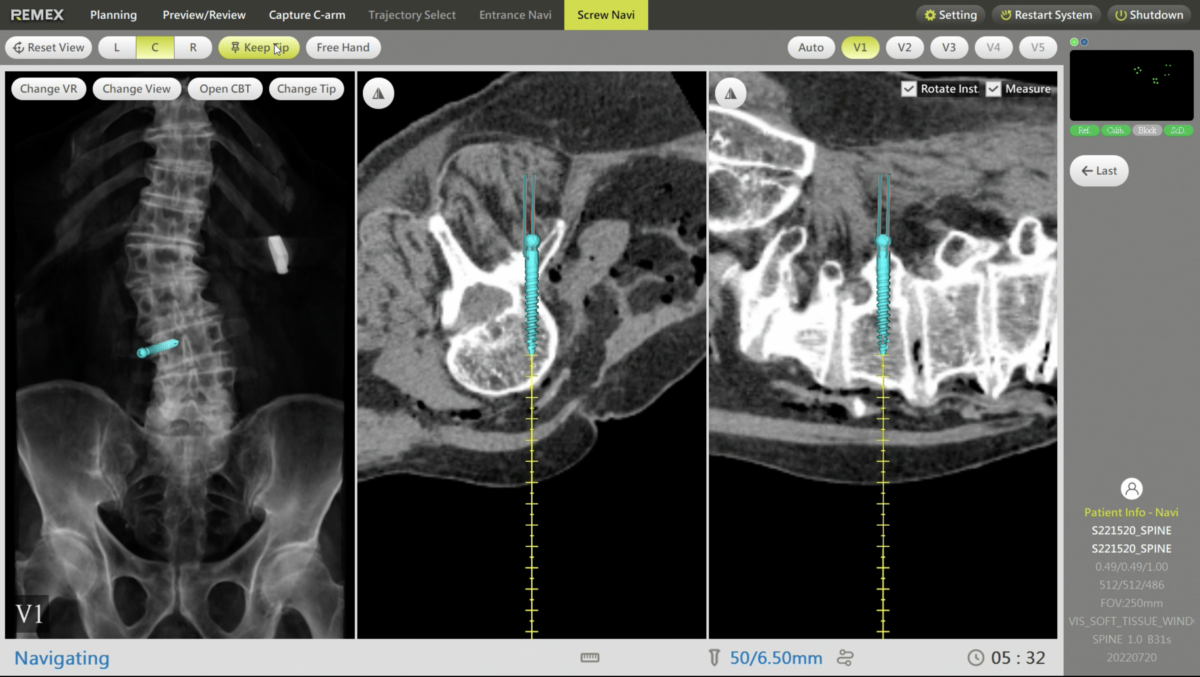

Precisión en la colocación de tornillos

Guía de imágenes en tiempo real durante todo el proceso de colocación de tornillos pediculares.

Navegación en tiempo real

Selecciona la trayectoria con guía en tiempo real y verifica con el arco en C.

Navegación 3D en tiempo real

Después de una verificación sencilla de los instrumentos, estos junto con los implantes se visualizarán claramente en tiempo real. La posición relativa de todos los dispositivos y del paciente estará bajo control y se mostrará en visores de imagen únicos para distintos procedimientos quirúrgicos.